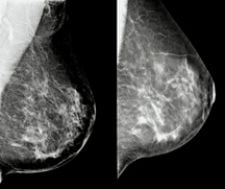

Because the radiologist can easily manipulate the contrast on the Selenia system, they are seeing much more detail, in much less time. Greater contrast control is especially important when dealing with patients with denser breast tissue, or implants. These patients, in the past, had presented challenges for both technologists and radiologists.

Tomosynthesis uses the digital platform to capture a series of images, exposed in an arc around the breast. The data collected is then reconstructed into a detailed three-dimensional image of the breast. Similar to a CAT scan, the reconstructed images are made up of a series of thin slices, which can be manipulated and viewed in a number of different ways for more detailed analysis.

“A lot of the problems with mammography stem from tissue overlap,” Poplack said, “but if you can unravel the tissue or eliminate the overlap, then you can avoid recalling a lot of patients who don’t really need to be recalled. Tomosynthesis is going to reduce the number of false positive screening exams.”

Because the images can be taken apart and examined individually, tomosynthesis is also expected to detect cancers earlier than with standard mammograms. “In some instances,” Poplack said, “overlying tissue may be obscuring a small cancer. By being able to get a slice-by-slice look at the breast, you may then uncover the cancer that was hidden by the overlying tissue.” He added, “Tomosynthesis will probably allow us to find more breast cancers earlier.”